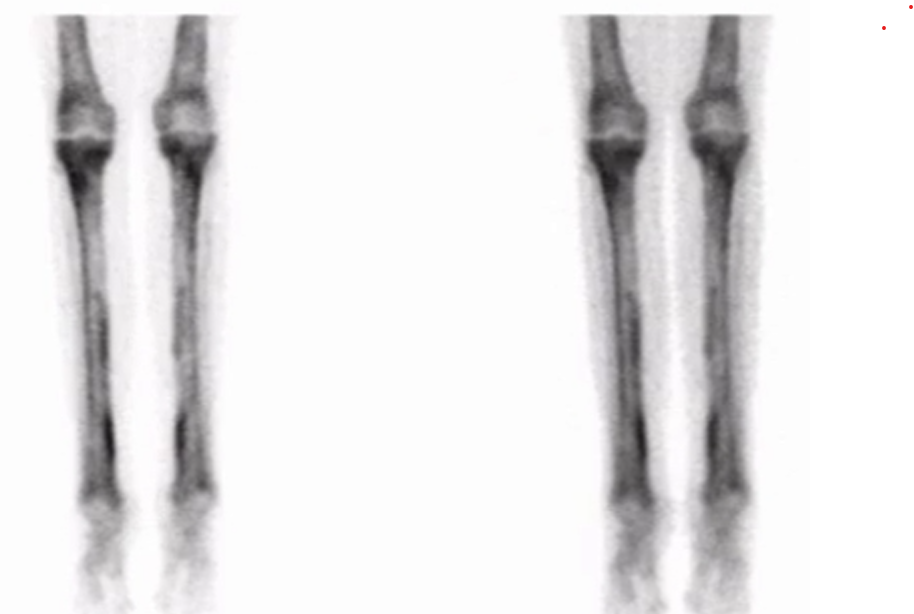

Shin Splints (Medial tibial stress syndrome)

• Seen as diffuse uptake in the posterior-medial tibial cortex

• Best visualized on the delayed static images

• Note: stress fracture will typically have early uptake

• Arterial and blood pool images are normal